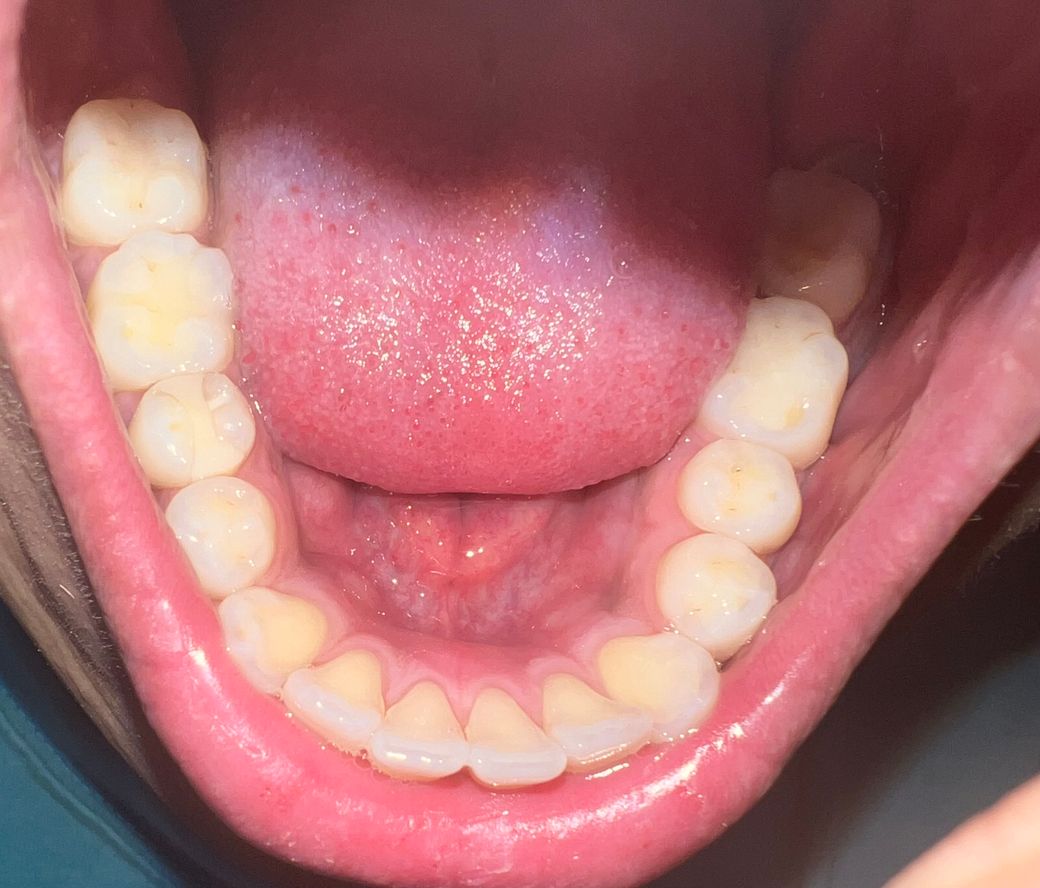

잇몸에 주름같은게 있어요 무슨 질병인가요?

잇몸에 주름 같은것이 생기고 아랫쪽 앞니 안쪽의 잇몸이 욱신거리면서 아파요. 아픈지는 일주일 정도 됐어요 다른 질병때문에 항생제를 복용중 입니다.

현재 사진상으로는 크게 문제가 되어 보이지는 않습니다. 하지만 잇몸에 통증이 있는 경우에는 잇몸에 염증이 있을 가능성이 높기에 통증 및 붓기 지속시에는 치과 진료를 받길 권합니다.

사진상으로 보면 큰 문제는 없습니다. 욱신거리는건 대부분 잇몸에 염증이 잇을때 나타나는 현상이며 치과에 가셔서 스켈링 및 잇몸치료받으시면됩니다.

임상사진 상으로 큰 이상 소견이 보이지는 않습니다만, 임상검사 및 방사선검사를 받아보셔야 정확히 진단할 수 있습니다. 치과에 방문해주세요.